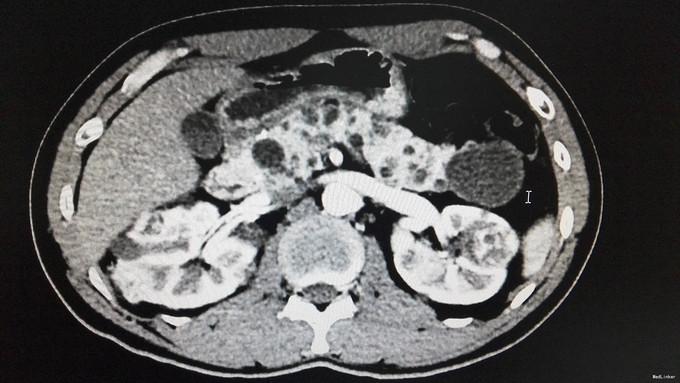

查体:背部后正中线上长7cm手术瘢痕。双肾区无红肿、隆起,左肾区压痛、叩痛,右肾区无压痛、叩痛,左肋脊点、肋腰点压痛,右肋脊点、肋腰点无压痛。左侧上中输尿管点压痛,右侧上中输尿管点无压痛,膀胱区无压痛。辅查:门诊CT示:1、胰腺多发囊肿,双肾多发肾癌,双肾多发囊肿,考虑VHL综合征。2.肝S2/4异常强化灶,考虑异常灌注。家族史:父亲肾癌去世。

诊断:VHL综合征

VHL综合征就是“Von Hippel-Lindau综合征”的简称,即CNS血管母细胞瘤合并肾脏或胰腺囊肿、嗜铬细胞瘤、肾癌以及外皮囊腺瘤等疾病。 VHL综合征是一种罕见的常染色体显性遗传性疾病,疾病是因位于染色体3P25.3的VHL抑癌基因发生突变所致。VHL的临床表现和症状包括血管瘤、血管母细胞瘤、嗜铬细胞瘤、肾细胞癌,胰腺囊肿(胰腺浆液性囊腺瘤)以及咖啡牛奶斑。VHL综合征患者平均寿命不超过49岁。其主要死亡原因是中枢神经系统血管母细胞瘤破裂出血、肾细胞癌和嗜铬细胞引起的恶性高血压。本例患者脊髓血管母细胞瘤,肾脏或胰腺囊肿,肾癌,结合家族史诊断VHL基本明确。 治疗上,中枢神经病变根据部位行手术或X刀、伽玛刀治疗。嗜铬细胞瘤应手术切除。肾细胞癌的治疗与散发性肾细胞癌有所不同,由于前者常为双侧多发,肿瘤生长较慢,转移较晚,故即使为单侧肾癌,也应尽量行保留肾单位的肿瘤切除手术,因为对侧也有在今后发生肾肿瘤的可能。多年临床观察发现,双侧全肾切除会诱发或加快其它部位的VHL肿瘤的生长,主要认为是由于移植术后的免疫抑制治疗和应用透析的结果。VHL综合征胰腺囊肿无恶变倾向,应不予处理。 VHL基因突变的人群携带率估计为3/10万左右,外显率接近100%。其遗传特征为常染色体显性方式,子女有50%机率发病,故对其子女也应严密随访。